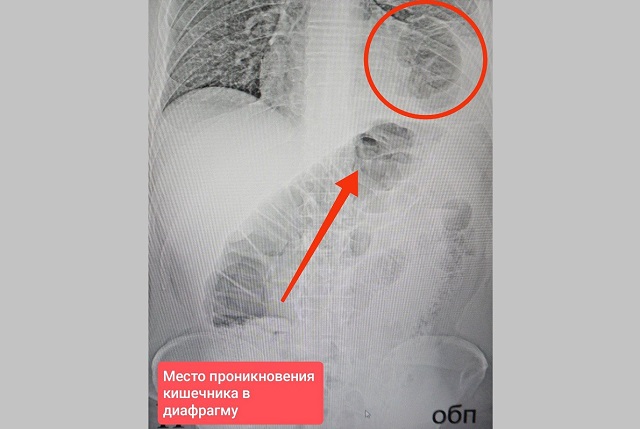

Врачи хирургического отделения №2 Нижнекамской ЦРМБ спасли 46-летнего пациента с необычной грыжей: часть толстого кишечника пациента находилась в грудной клетке.

Медики пояснили, что мужчина обратился в больницу с сильными болями в животе, которые не снимались даже обезболивающими. В ходе обследования выяснилось, что у мужчины была ущемленная грыжа диафрагмы — редкое состояние, при котором органы брюшной полости через отверстие в диафрагме попадают в грудную клетку.

Вероятная причина сложившейся ситуации — ножевой удар в грудь, полученный еще в 2017 году. Тогда лезвие, пройдя через легкое и диафрагму, оставило после себя небольшое отверстие. Со временем в него проникла петля кишечника, что привело к кишечной непроходимости — опасному состоянию, угрожающему жизни.

Врачи аккуратно извлекли ущемленную кишку из грудной клетки, проверили, нет ли омертвевших участков (некроза). После устранили дефект диафрагмы, зашив отверстие. Операция длилась два часа и прошла успешно. Пациент уже идет на поправку.